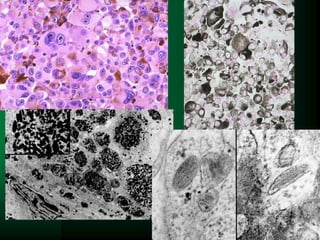

PLASMOCYTOMA

APUD